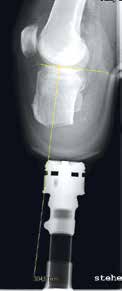

Ziel dieses Beitrages ist die Empfehlung eines Paradigmenwechsels in der postoperativen Behandlung auf der Grundlage jahrzehntelanger operativer und rehabilitativer Erfahrung in den ersten drei bis sechs Monaten nach der Amputation – wobei zu bedenken gilt, dass es eigentlich kein „echter“ Paradigmenwechsel ist, da die unten dargelegten Empfehlungen früher bereits praktiziert wurden und sich bewährt haben (Abb. 1 u. 2).